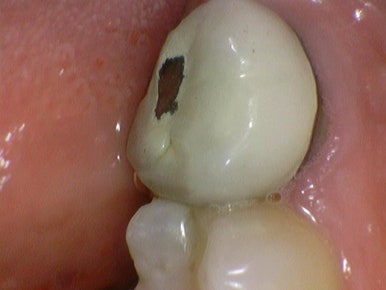

예전에 사용되었던 PFM 크라운

예전에는 금니가 보이기 싫으니 메탈에 도자기를 올린 PFM크라운을 사용해서

위의 사진처럼 도자기가 깨지거나

또는 메탈이 잇몸쪽에도 보이기도 했으나

지르코니아크라운은 PFM의 도자기보다 내구성이 좋고

통으로 하얀색이기 때문에 그럴 염려가 없습니다.

깨진 치아의 지르코니아 크라운 치료/ 시청역치과